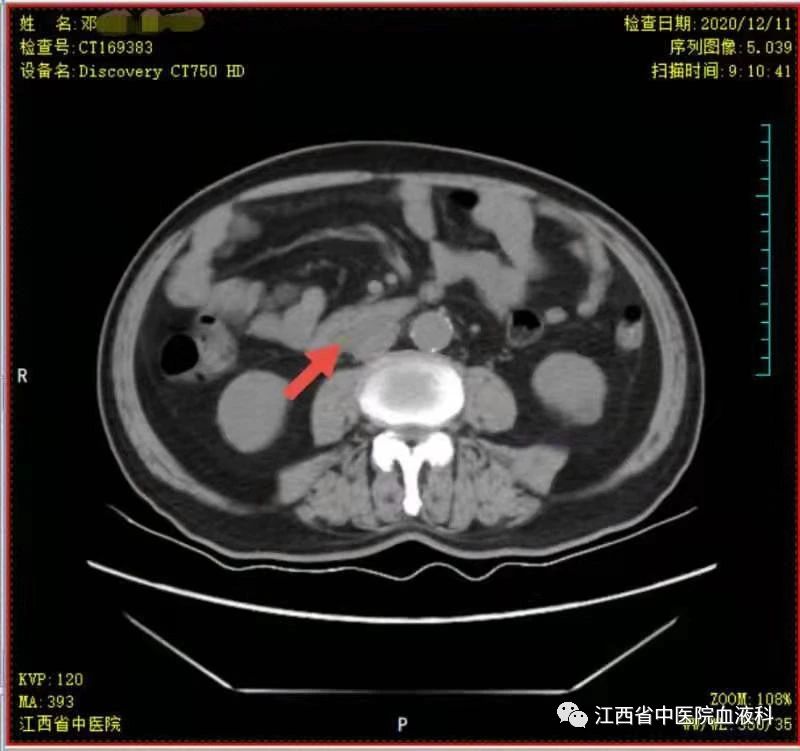

2020年10月中旬邓大爷在家人的陪同下来我科就诊,全腹部增强CT提示:右侧睾丸切除术后复查:1.腹膜后(胰头后下方)、双侧肾上腺区团块状异常强化影。2.肝左内叶上段小囊肿,双肾小囊肿,较前相仿。3.右侧腹股沟前方、皮下条索、小片影,境界不清,较前减小,拟为术后改变。4.右下腹腔少许钙化淋巴结,较前相仿。因病情危急,考虑邓大爷高龄、体能差、窦性心动过缓(平均心率50次/分)心脏功能差等情况,经讨论于2020-10-24起第一次行减剂量方案R-miniCHOP(利妥昔单抗700mg d0、环磷酰胺700mg d1、多柔比星40mg d1、长春瑞滨20mg d1、地塞米松10mg d1-5)方案。第一次化疗后评估病情,腹腔瘤体缩小了2/3,取得了很好的治疗效果,可邓大爷心脏却亮起了红灯,经过了积极护心等支持治疗后,大爷心脏功能有所恢复。遂于2020-11-19、2020-12-10行2次R-miniCOP方案(去除了具有心脏毒性的多柔比星),三次化疗结束后予评估病情,提示腹腔包块明显缩小,淋巴瘤病情有所好转。